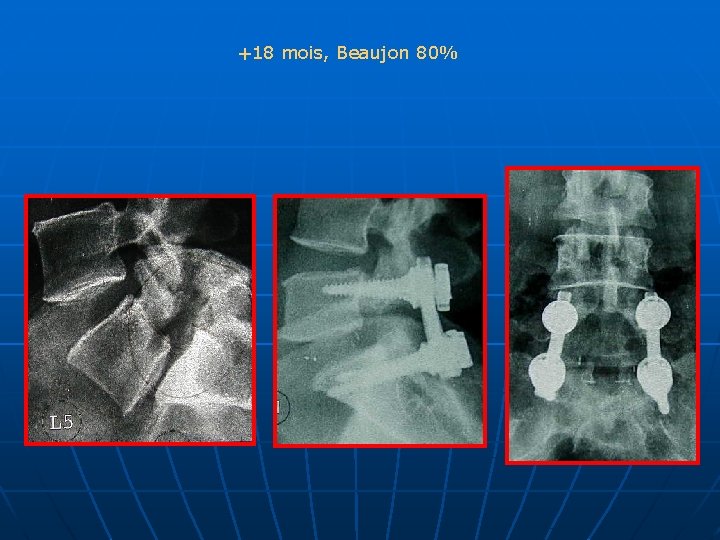

+18 mois, Beaujon 80%

CONCLUSION n n LOMBALGIES ISOLEE: Rx standard RADICULALGIES: Rx dynamiques, grand format, IRM: étude du disque sus jacent pour l’étendue de l’arthrodèse